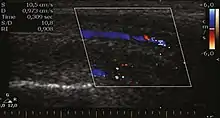

Venous drainage is performed by the deep and superficial dorsal veins of the penis. The dorsal arteries of the penis are located adjacent to the deep dorsal vein and a cavernous artery is located in the center of each corpus cavernosum. On color Doppler, the cavernous arteries present single phase flow. In the flaccid penis (Figure 3), the normal cavernous arteries show a systolic peak between 11 and 20 cm/s. At the beginning of erection, the systolic and diastolic flows undergo progressive increases. When vein occlusion begins, the diastolic flow decreases progressively, and once stiffness is established, it becomes negative.[1]

Figure 3: Longitudinal, ventral ultrasound of the penis, with pulsed mode and color Doppler. Normal flow pattern of the cavernous artery in a flaccid penis.[1]